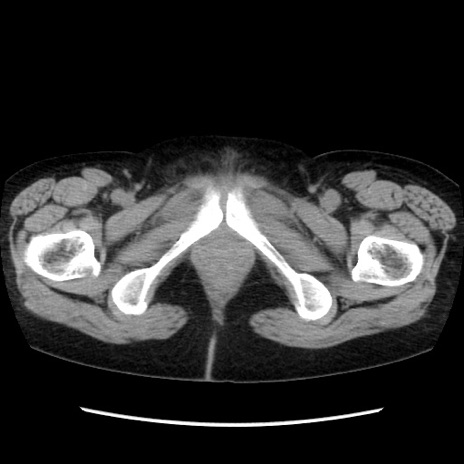

症例32(横断像)

【症例】40歳代 女性

【主訴】上腹部痛、嘔気・嘔吐

【現病歴】約9時間前頃から急に上腹部痛、嘔気、嘔吐が出現。改善しないため救急要請。

【既往歴】子宮頚癌(広汎子宮全摘術、放射線療法)、腸閉塞